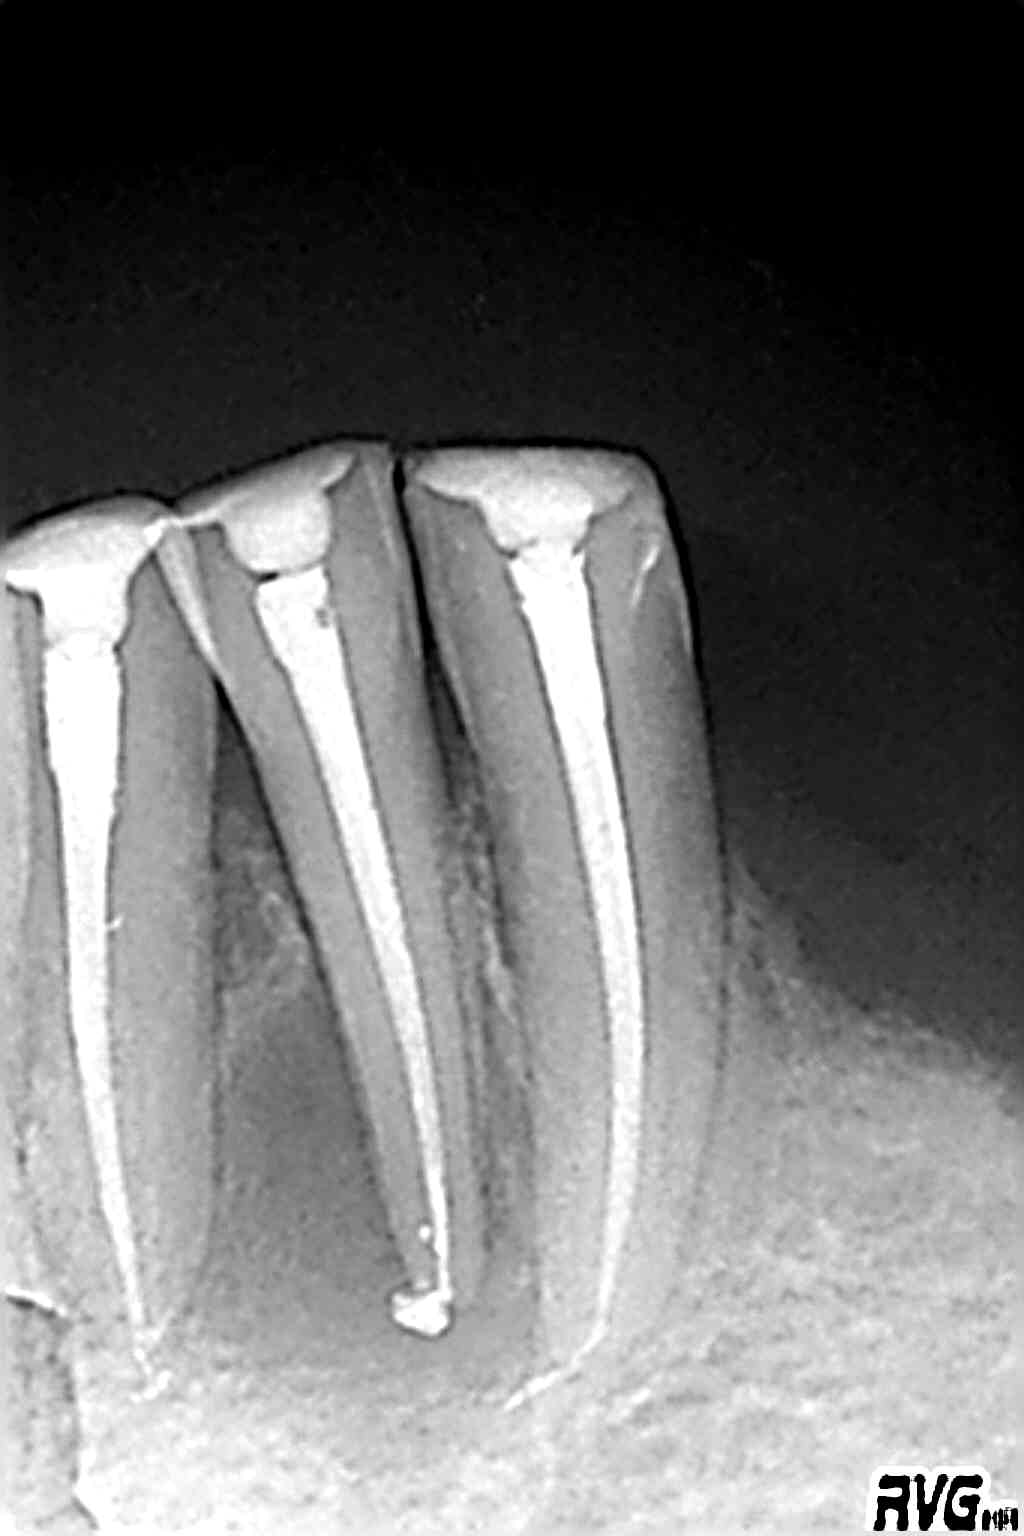

J'ai mon vieux capteur trophy (dont j'étais très satisfait) qui m'a lâché. Première image.

Par ex endo 26

Deux radios : la première avec l'ancien capteur trophy

et la seconde avec le nouveau 6100.